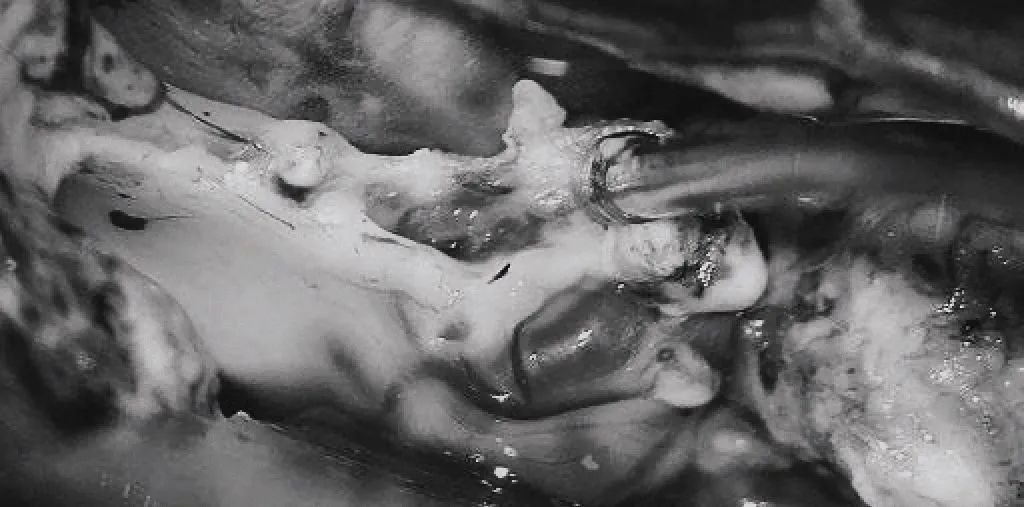

▼(e)将AVM后缘向前牵离穹窿。

▼(f)在透明隔底部保留FoM、穹窿和右侧SepV。